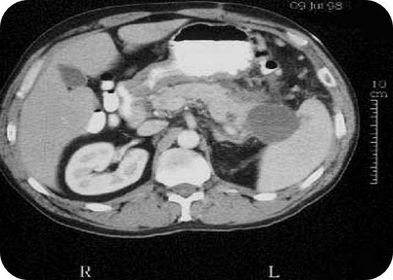

ENFERMEDAD DE HIGADO POLIQUISTICO

CARCINOMA HEPATOCELULAR

TUMOR TROFOBLÁSTICO

EQUINOCOCOSIS RENAL

CIRROSIS MACRONODULAR